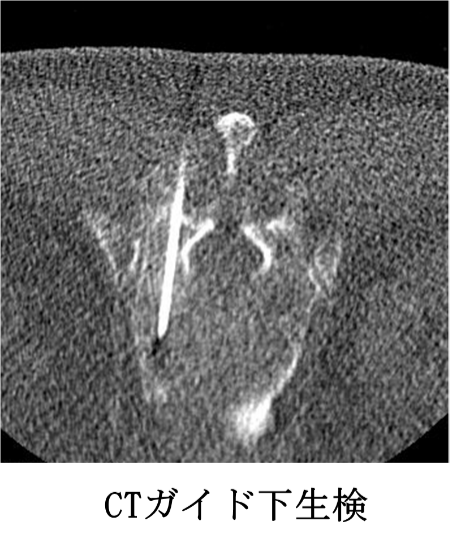

CTガイド下針生検